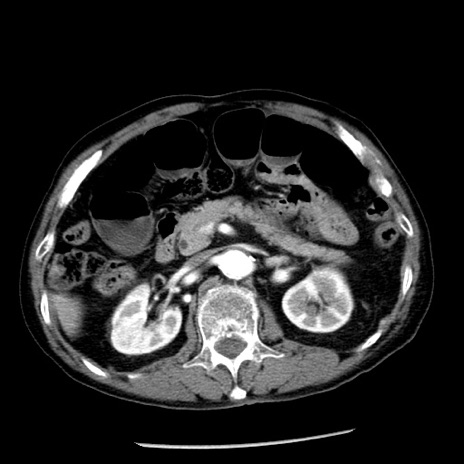

症例26(横断像)

【症例】80歳代男性

【主訴】嘔吐

【現病歴】昨晩2回嘔吐あり、今朝になっても嘔吐あり。来院。

【既往歴】胃潰瘍

【身体所見】意識清明、BT 37.6℃、BP 166/95mmHg、HR 100bpm、SpO2 97%、腹部:平坦・軟、腸蠕動音聴取良好、圧痛なし。

【データ】WBC 21900、CRP 1.46